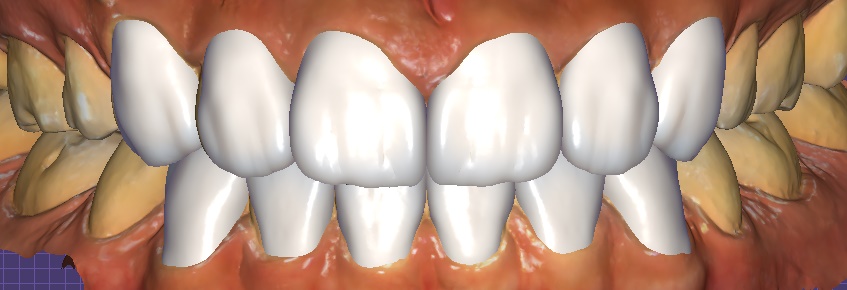

① 디지털 스캔 & 디자인

– 구강스캐너로 정밀한 데이터 채득 → 3D 디자인 및 시뮬레이션

오브제로 라미네이트 시뮬레이션